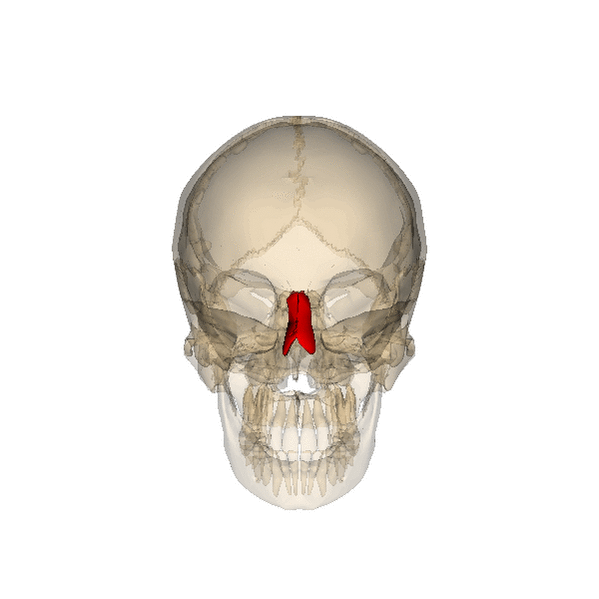

Носовая кость

Носовая кость — парная, четырёхугольная, немного удлиненная и — несколько выпуклая спереди кость лицевой части черепа. Образует переднюю стенку скелета носа, формируя переносицу и верхнюю часть спинки носа.

Носовые кости человека

Носовые кости составляют остов передней стенки корня и верхней трети спинки наружного носа. Участвуют в образовании передней части верхней и латеральной стенок носовой полости[1].